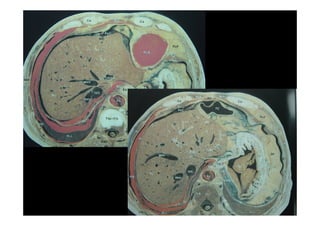

ANATOMIA SEGMENTAR DO FÍGADO

(COUINAUD)

• LOBO CAUDADO SEG. I

• SEGMENTO SUPERIOR LATERAL ESQUERDO SEG.II

• SEGMENTO INFERIOR LATERAL ESQUERDO SEG III

• SEGMENTO MEDIAL ESQUERDO SEG IV

• SEGMENTO INFERIOR ANTERIOR DIREITO SEG V

• SEGMENTO SUPERIOR ANTERIOR DIREITO SEG VII

• SEGMENTO INFERIOR POSTERIOR DIREITO SEG VI

• SEGMENTO SUPERIOR POSTERIOR DIREITO SEG VIII